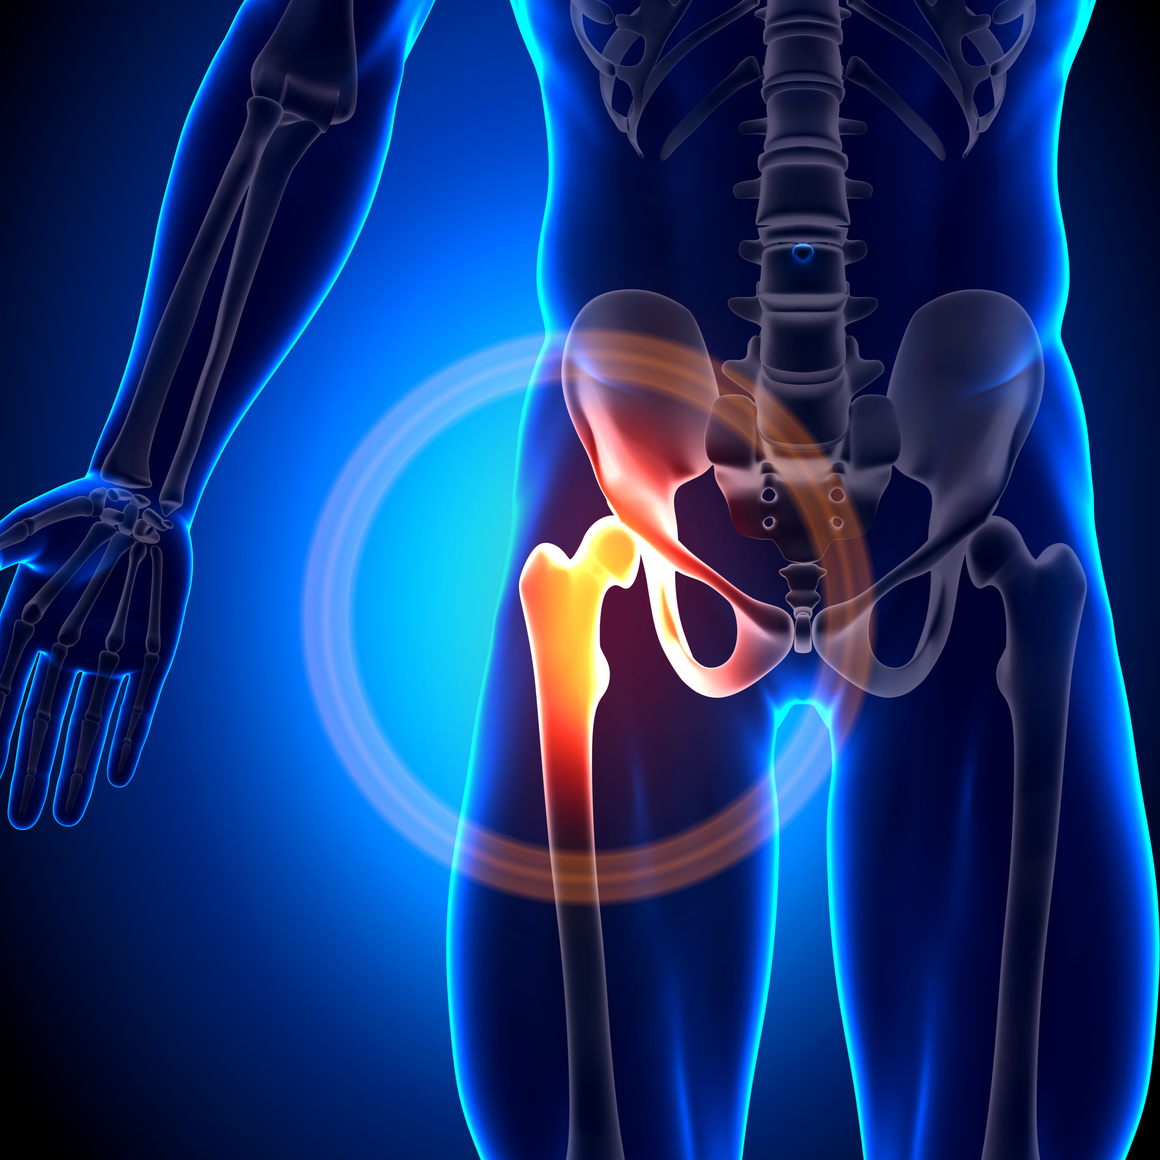

他関節症との同時治療可

ひざのみならず、股関節痛や足首などの関節痛について、同時に治療を行うことが可能です。